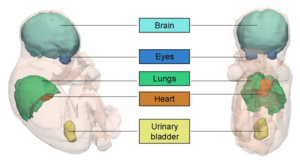

MRI-Only Based Radiotherapy Treatment Planning for the Rat Brain on a Small Animal Radiation Research Platform (SARRP)

Publication: PLoS One. 2015 Dec 3;10(12):e0143821. PMID: 26633302 | PDF Authors: Gutierrez S, Descamps B, Vanhove C. Institution: Medical Image and Signal Processing Group, Ghent University-iMinds Medical IT department, Ghent, Belgium. Background/Purpose: Computed tomography (CT) is the standard imaging modality in radiation therapy treatment planning (RTP). However, magnetic resonance (MR) imaging provides superior soft tissue contrast, increasing the precision of target volume selection. We present MR-only based RTP for a rat brain on a small animal radiation research platform (SARRP) using probabilistic voxel classification with multiple MR sequences. Six rat heads were imaged, each with one CT and five MR sequences. The MR sequences were: T1-weighted, T2-weighted, zero-echo time (ZTE), and two ultra-short echo time sequences with 20 μs (UTE1) and 2 ms (UTE2) echo times. CT data were manually segmented into air, soft tissue, and bone to obtain the RTP reference. Bias field corrected MR images were automatically segmented into the same tissue classes using a fuzzy c-means segmentation algorithm with multiple images as input. Similarities between segmented CT and automatic segmented MR (ASMR) images were evaluated using Dice coefficient. Three ASMR images with high similarity index were used for further RTP. Three beam arrangements were investigated. Dose distributions were compared by analysing dose volume histograms. The highest Dice coefficients were obtained for the ZTE-UTE2 combination and for the T1-UTE1-T2 combination when ZTE was unavailable. Both combinations, along with UTE1-UTE2, often used to generate ASMR images, were used for further RTP. Using 1 beam, MR based RTP underestimated the dose to be delivered to the target (range: 1.4%-7.6%). When more complex beam configurations were used, the calculated dose using the ZTE-UTE2 combination was the most accurate, with 0.7% deviation from CT, compared to 0.8% for T1-UTE1-T2 and 1.7% for UTE1-UTE2. The presented MR-only based workflow for RTP on a SARRP enables both accurate organ delineation and dose calculations using multiple MR sequences. This method can be useful in longitudinal studies where CT's cumulative radiation dose might contribute to the total dose. |

Illustration of a CB-CT and five MR images of the same animal. a) Coronal CB-CT image and (b)-(f) biased field corrected and masked coronal MR images using a T1-weighted (b), T2-weighted (c), ZTE (d), UTE1 (e) and UTE2 (f) sequence. All CB-CT images were first co-registered using 3D Slicer version 3.6.3 by rigid body transformations using normalized mutual information. |